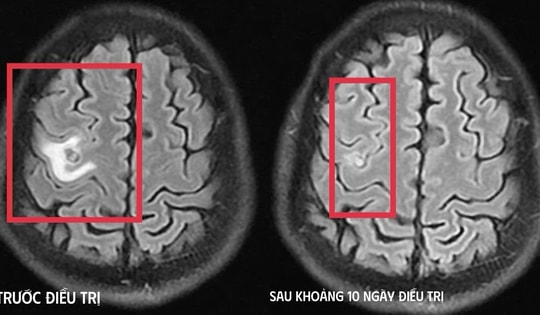

Co giật do sán làm tổ trong não

23/12/2025 14:44

Người đàn ông 39 tuổi bỗng xuất hiện đau đầu dữ dội, co giật, tưởng là u não, khi kiểm tra bác sĩ phát hiện ổ sán ký sinh.